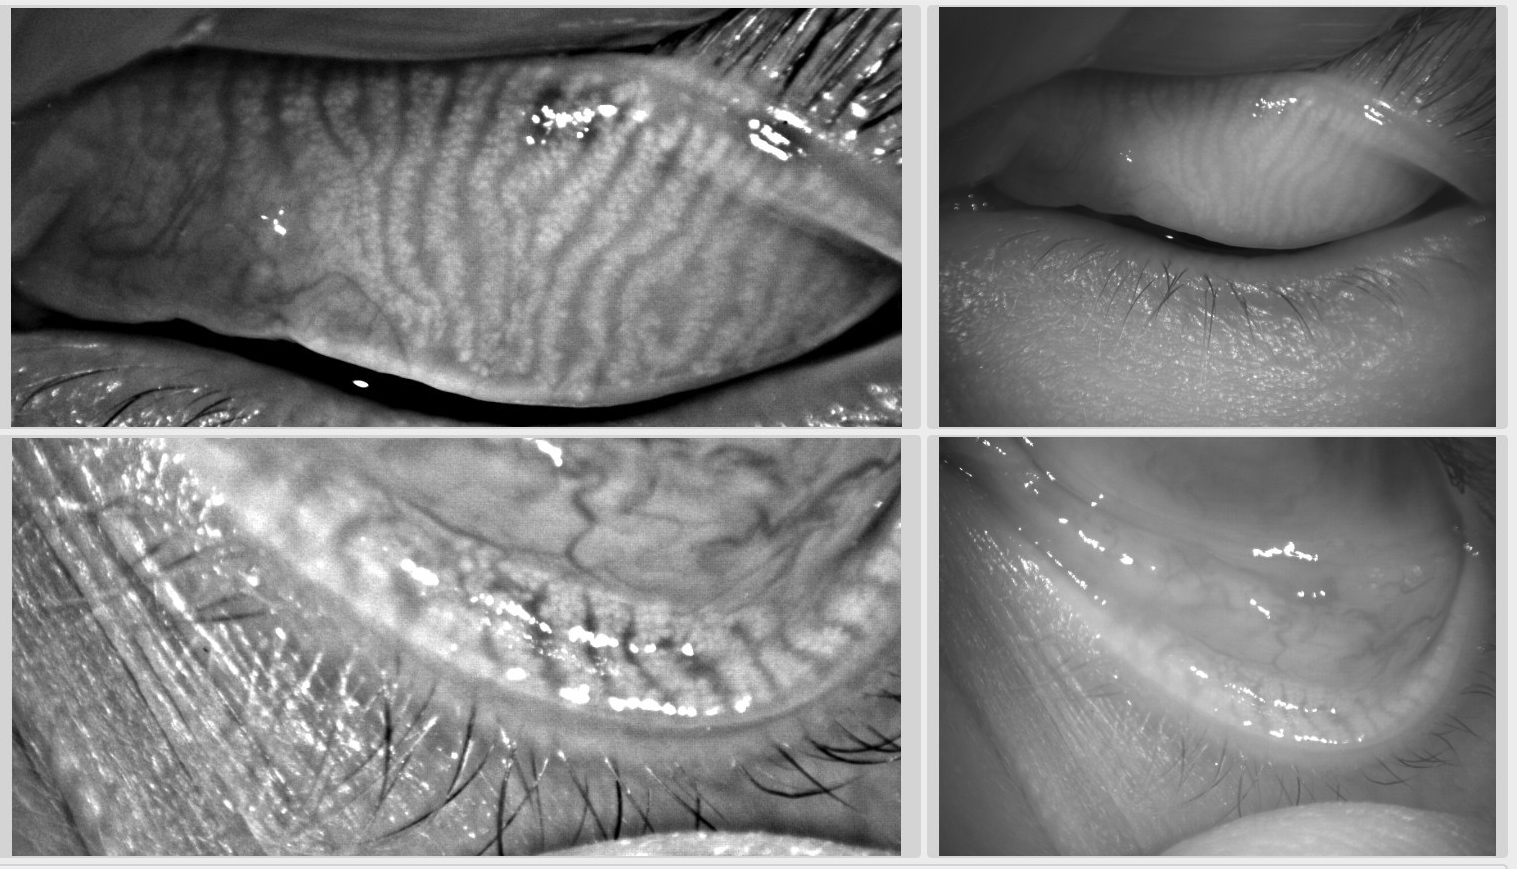

EXÁMEN EN LÁMPARA DE HENDIDURA

La detección de anomalías que afectan el párpado, los márgenes palpebrales anterior y posterior, la conjuntiva y la córnea observadas durante el examen de la lámpara de hendidura ofrece una visión hacia un diagnóstico diferencial de subtipos de Síndrome de Disfunción Lagrimal (DTS).

INTERFEROMETRÍA Y MEIBOGRAFÍA

La interferometría es una técnica no invasiva que puede usarse para medir el espesor de la película lagrimal mediante el uso del principio de interferencia óptica o la interacción de las ondas luminosas. La capa de lípidos de la lágrima puede generar imágenes a color de la capa superficial de la película lagrimal para evaluar su espesor a través de la superficie ocular (31). Una reducción en el grosor del componente lipídico de la película lagrimal (<60 nm) se ha correlacionado con la Disfunción de las Glándulas Meibomio asociado a Síndrome de Disfunción Lagrimal (DTS) (32). La actualización de los sistemas de diagnóstico permite la visualización de la glándula meibomiana a través de la Meibografía, ayudando además al diagnóstico diferencial de la Disfunción de las Glándulas Meibomio (33,34).